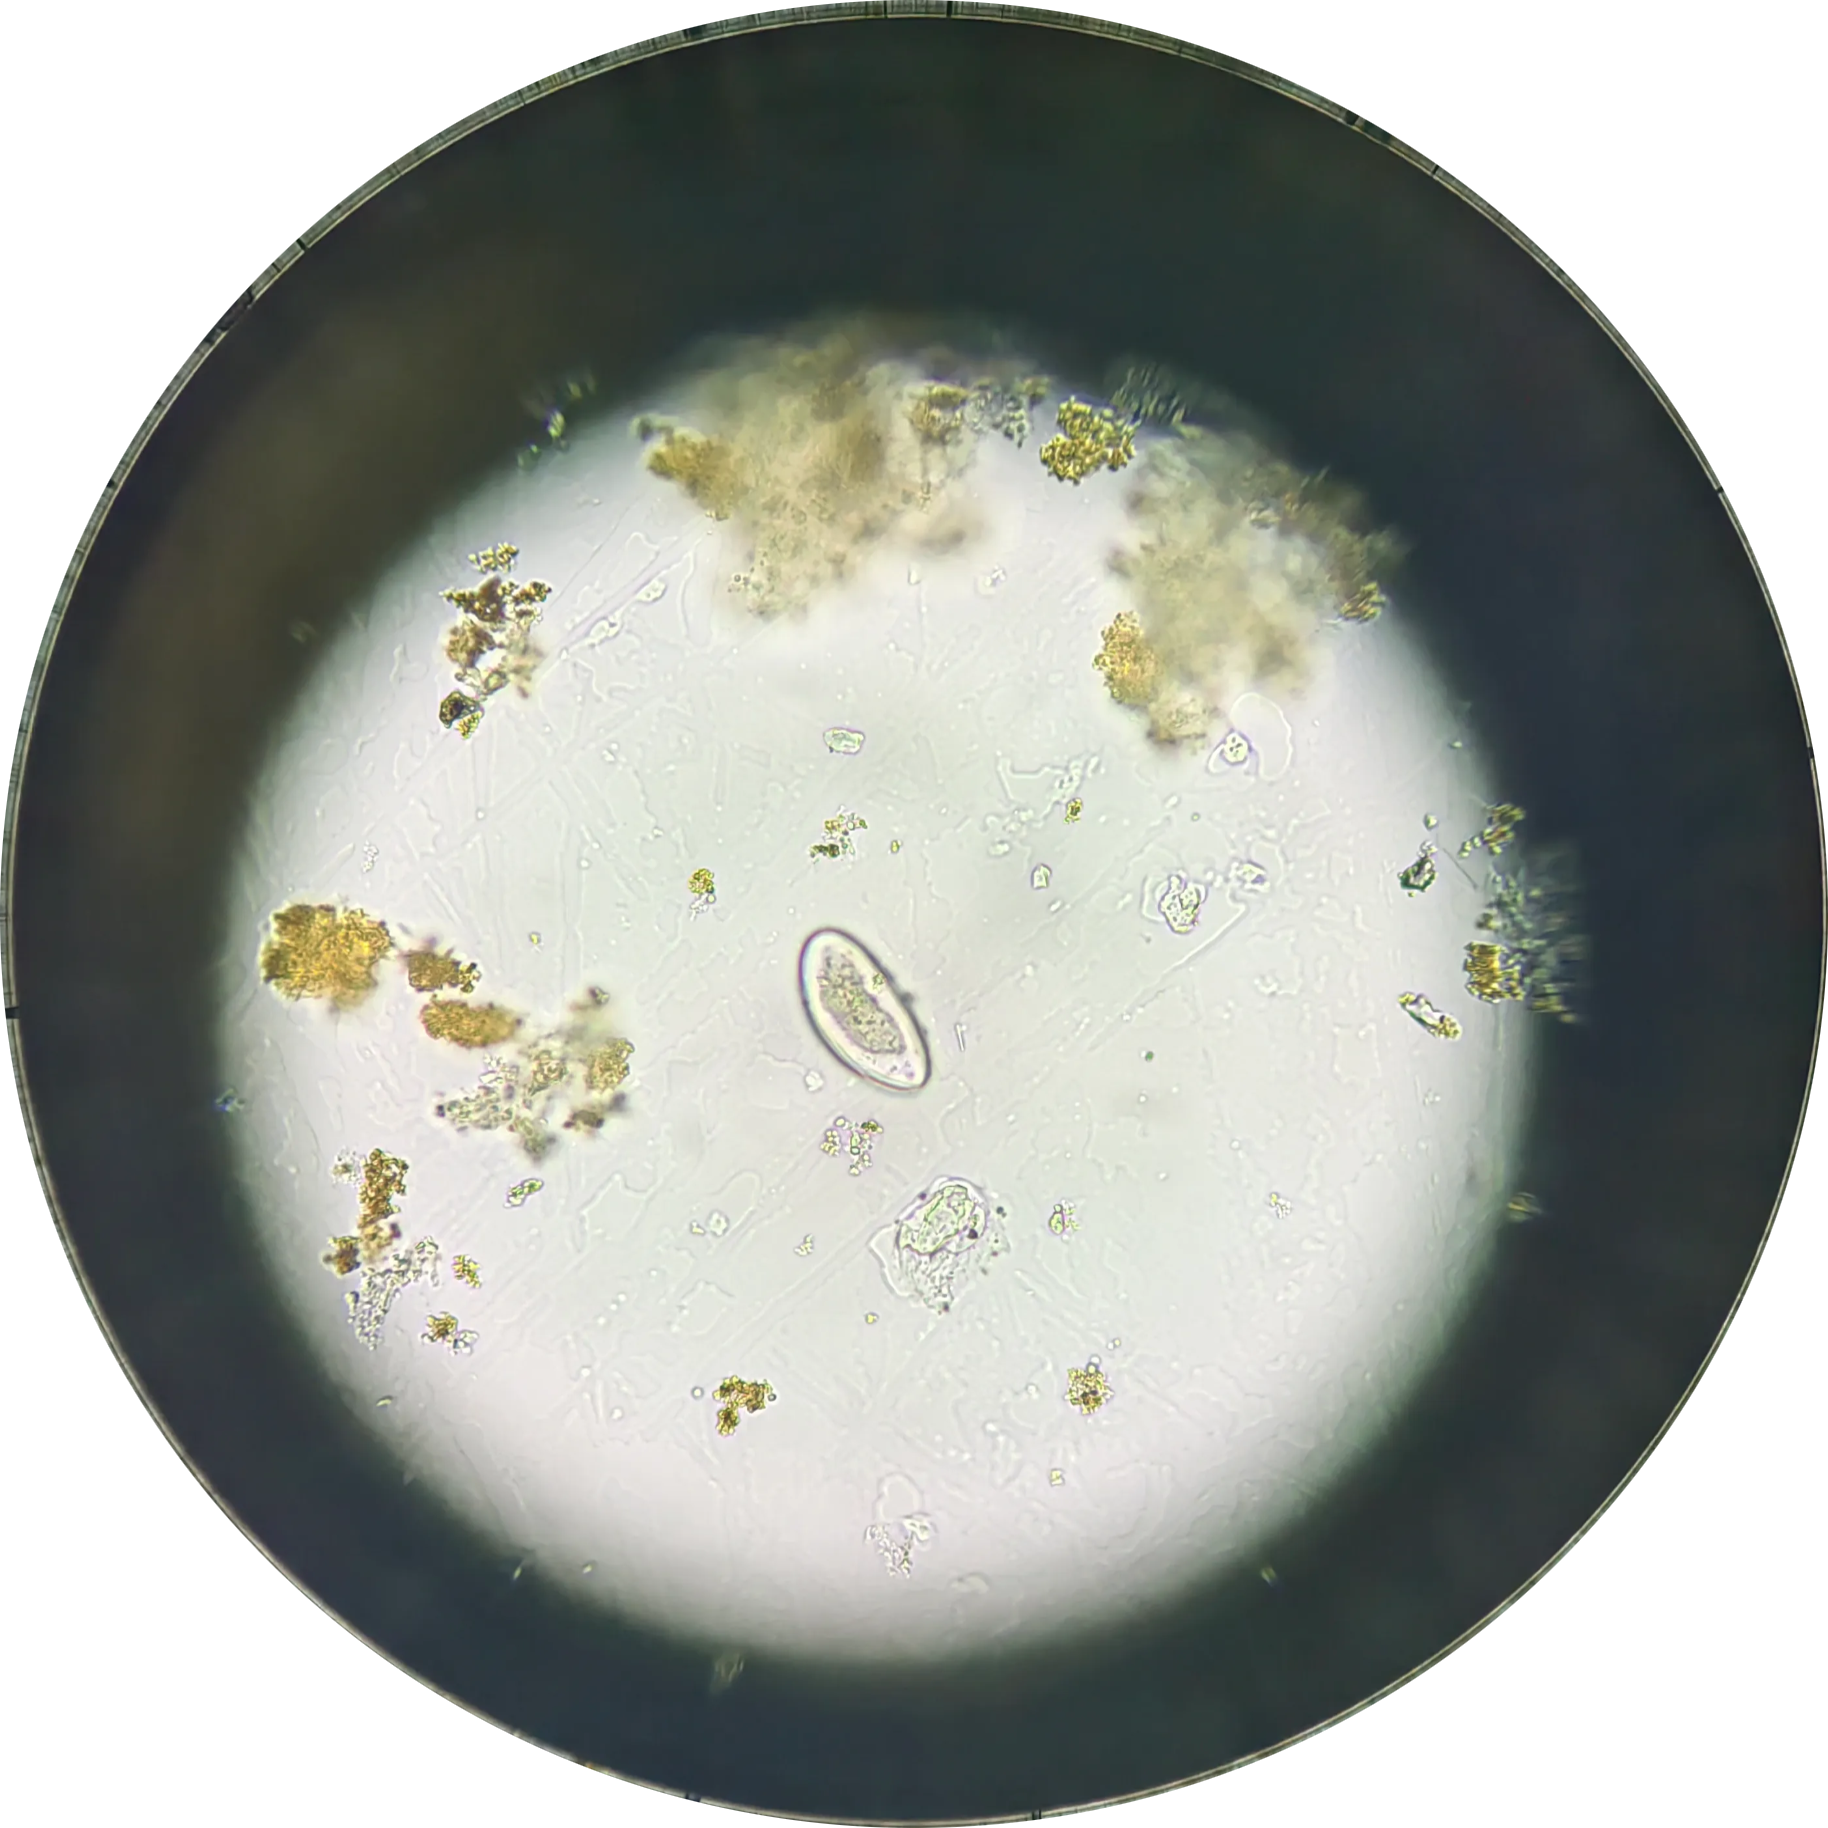

钩虫卵

💡

钩虫卵 壳薄,透明,多细胞,间隙明显

椭圆形,大小(57~76)μm× (36~40)μm,两端钝圆。卵壳较薄, 无色透明,卵内通常含2~4个卵细胞, 卵壳与卵细胞之间有明显空隙。在便秘者粪便内或粪便放置过久时,卵内细胞可继续分裂成桑葚状。两种钩虫卵形态相似,不易区别。